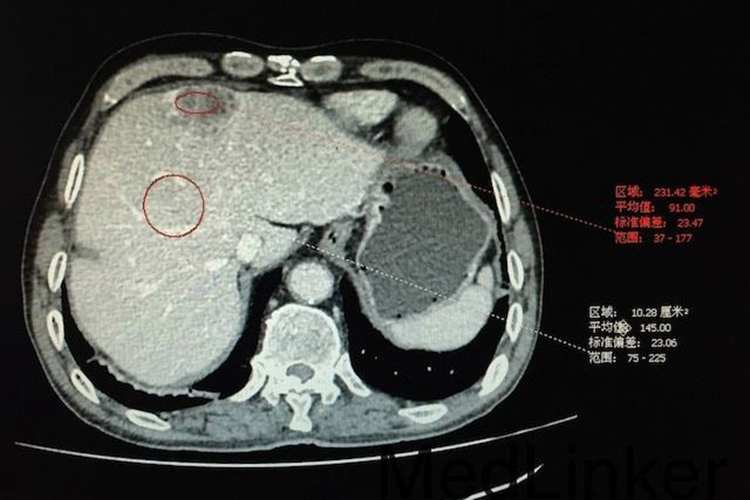

肝癌

肝癌表现为肝内局限的或多发的结节状或较大的肿块,CT平扫为低或等密度,巨块型者常有中心更低密度区,少数边界清楚并有假性包膜形成,增强后的动脉期可见肿瘤的实质部分强化,中心为不强化的低密度坏死区,其强化效应在静脉期和平衡期消失,静脉期还可以见到门静脉的癌栓征象。